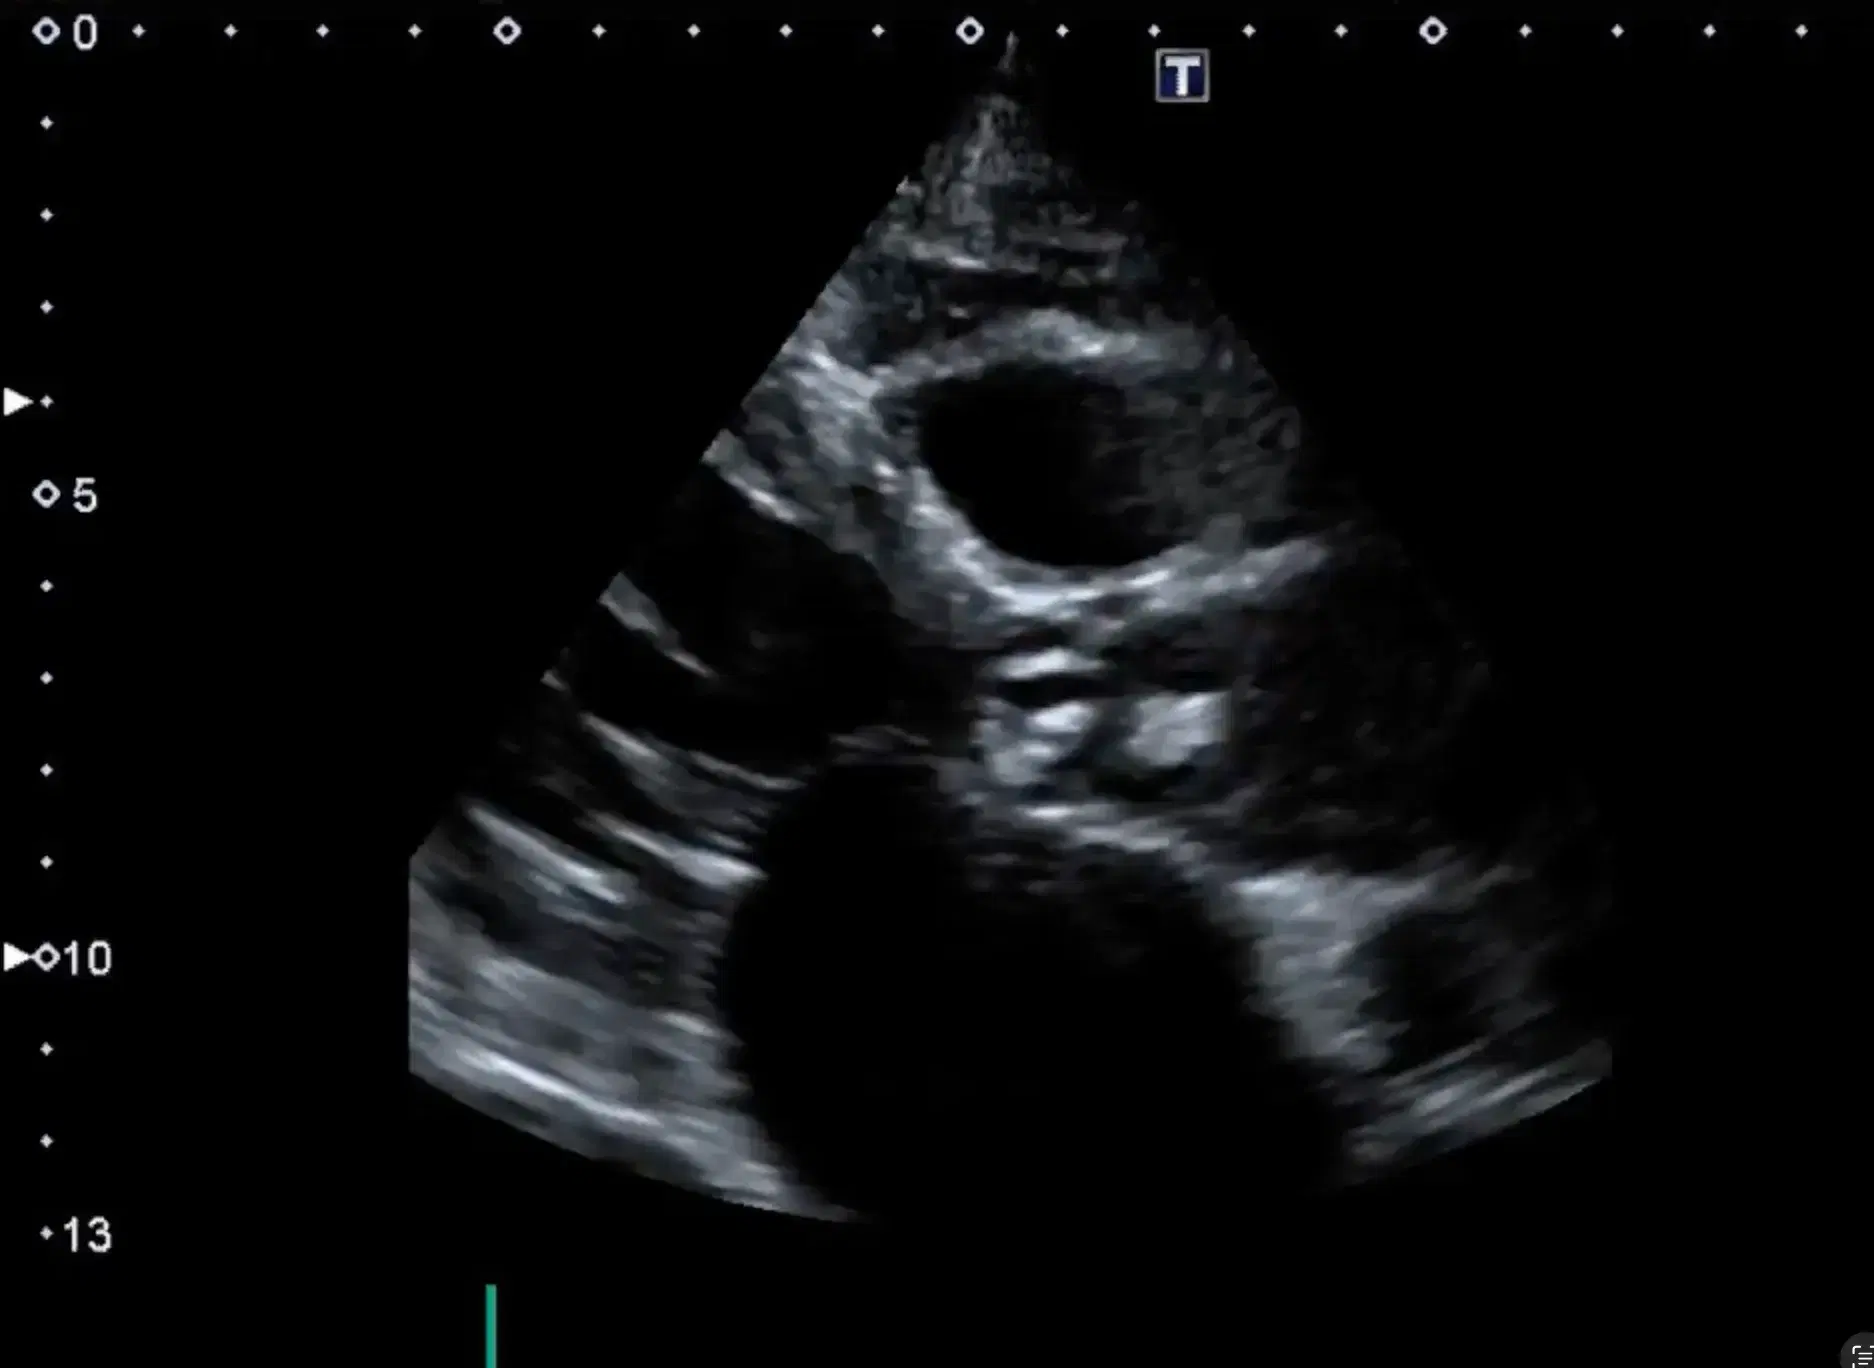

Learn to differentiate infective endocarditis manifestations, recognize signs in native valves, and assess using echocardiography through real patient cases.

Assess infective endocarditis using echocardiography